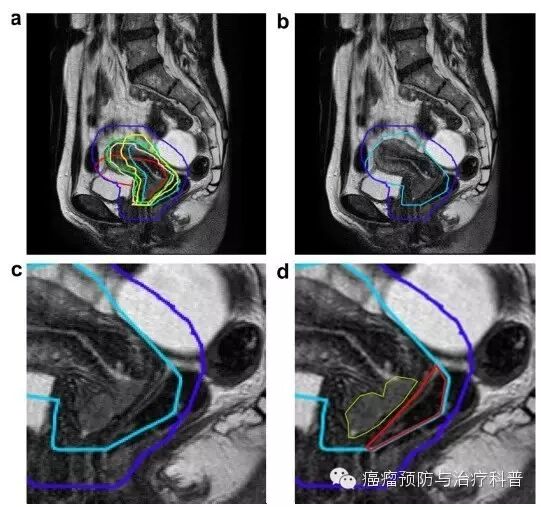

光子线束进入人体后主要发生康普顿效应为主,由于MR磁场的存在,因康普顿效应产生次级电子在洛伦兹力的作用下发生偏转。AJ Raaijmakers于2005在《Physics in Medicine & Biology》发表的文章可以知道,在射线束进入和离开模体的时候,能量沉淀与没有磁场情况下的剂量分布完全不一样,我们可以从PDD和Profile两方面看到这种区别。

4.2 磁场对次级电子的影响

(1)入射方向,在磁场作用下,结合2.1里面PDD曲线,可以清楚的看到建成区更靠近体表;

(2)出射方向,次生电子在洛伦兹力的作用下发生偏转,在体模-空气边界处回转再射入体模,导致在体模—空气边界处的剂量增高显著(电子返回效应,Electron Return Effect)。

4.3电子返回效应的临床问题和解决办法

由于电子返回效应的存在,组织—空气边界的局部剂量将会增高,这将是MRIgRT中一个非常重要的问题:

(1)射线在皮肤出口处的剂量会增高;

(2)体内空气腔(例如口鼻腔、气管、肺、直肠等)部位的剂量会增高。

研究者研究发现,对于电子返回效应,可以增加一个对侧野或者旋转照射来补偿电子返回引起的局部剂量增高的问题。

可以预见的是,MRLinac将要开展的不是普通放疗,一般会是IMRT,甚至VMAT,所以电子返回效应应该可以被很好的补偿。